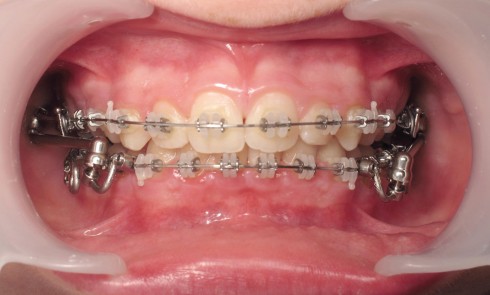

Article réservé à nos abonnés Traitement d’une classe II associant multibagues et Optimax Fix

Présentation Il s’agit d’un patient âgé de 13 ans qui présente une classe II-2 supraclusie associée à un encombrement mineur...